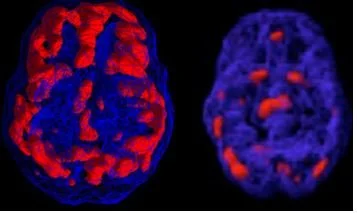

The image on the left is a brain stressed out in protective mode, the brain on the right is a brain in connection mode.

Your protective reactions are not random — they are patterns your body believes will protect you. Even if you know logically that you are just fine, something in your nervous system was coded in to say that when you see, hear, smell or sense xyz, it means danger, and you’ve got to do whatever you can to protect yourself. Thank heavens we have this survival instinct! It really does protect us when we see a car skidding on ice towards us, or when someone is screaming at us, or when we smell fire while we’re in the house.

The trouble comes when we know in our heads that we are ok, and we will be ok, but our system reacts anyhow. I like to say that the longest highway in the world is the one from our head to our heart. Thankfully, there are things we can do to help our nervous system (which we often think of as our emotions that come from our heart) to recognize only true cues of danger as such, and to also recognize cues of safety as they are intended like someone smiling at you while they hold the door open for you.